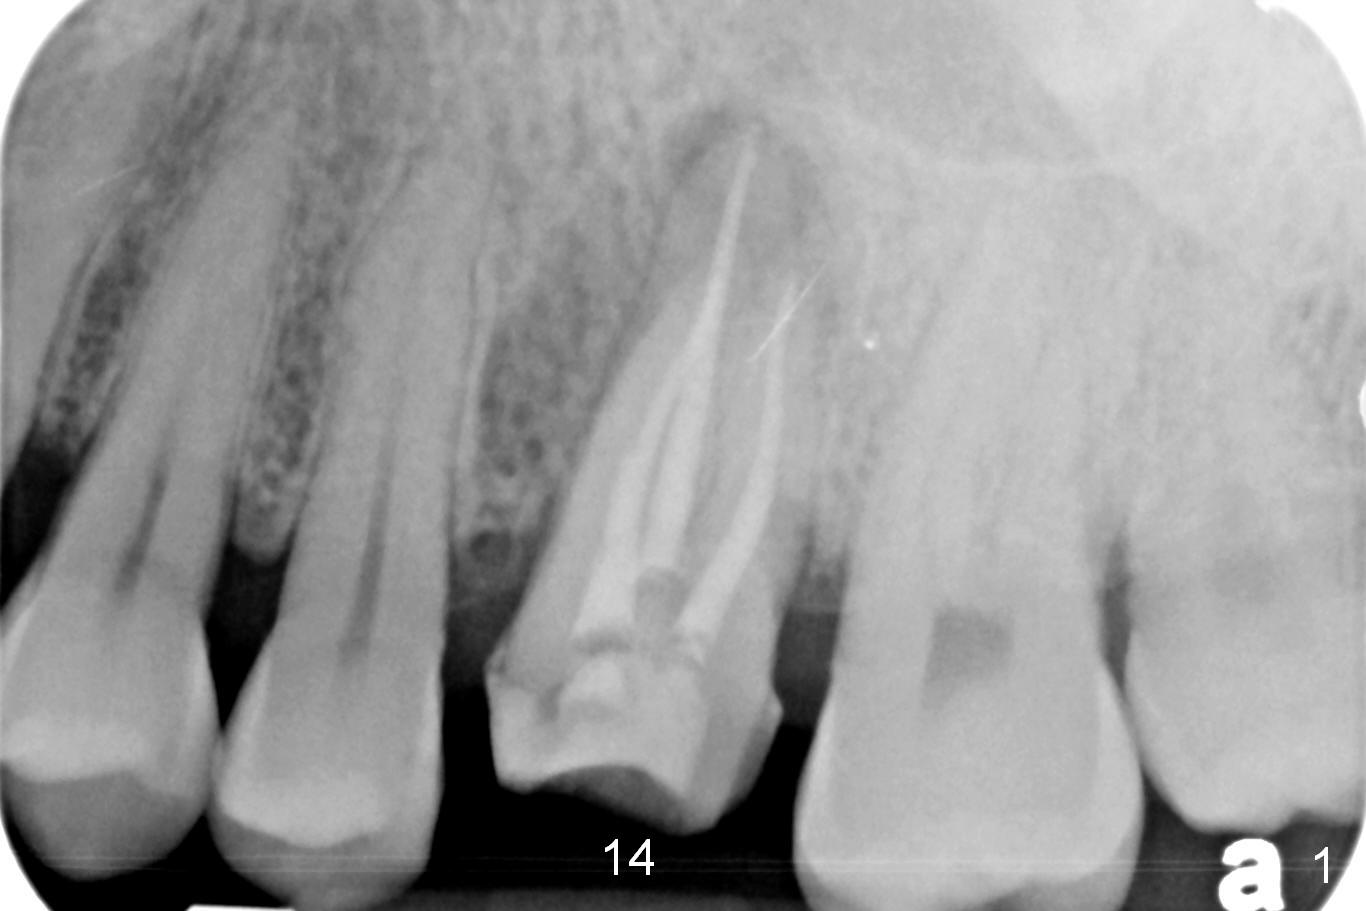

A 34-year-old man has persistent large periradicular radiolucency (Fig.1) after root canal therapy with a fistula (Fig.2). It appears that immediately after extraction (no Antibiotic) a long implant (15 or 16 mm, green outline) should be placed to bypass the bony defect with 2-point fixation (septum and sinus floor; Fig.3 (CBCT sagittal section), 4 (coronal section) red line). A shorter implant, which is placed at the septum (4-5 mm tall), is not expected to be stable. The diameter of the implant is to be determined after sequential osteotomy. The minimal will be 4 mm (Fig.5 axial section) as long as the implant or osteotomy does not perforate the palatal (P) or buccal (B) socket substantially. The bone density at the septum and the sinus floor is 1100 and 200-400 units, respectively. Drills and osteotomes (Tatum or Magic Expanders) will be used for osteotomy in these 2 segments, respectively.